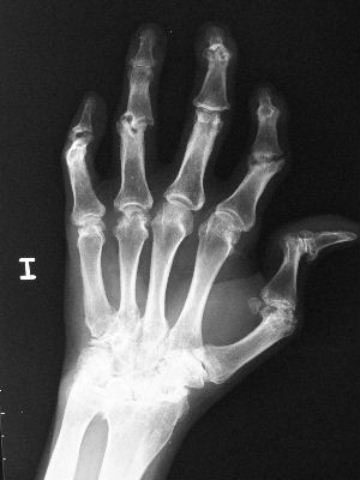

Artritis psoriásica y falange bífida.

Artritis psoriásica.